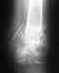

косорукость снимок